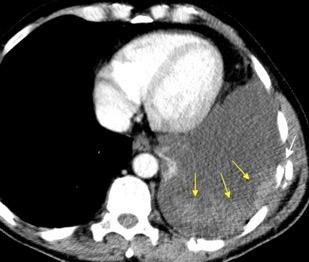

Marzo 2014: Perforación longitudinal distal secundaria a episodio de vómito (síndrome de Boerhaave). Derrame pleural izdo. que evoluciona a empiema.

Wang C-T et al. Tension hydropneumothorax in a Boerhaave syndrome patient: A case report . World J Emerg Med, 2021. Katabathina V et al. Nonvascular, nontraumatic mediastinal emergencies in adults:a comprehensive review of imaging findings. Radiographics. 2011.